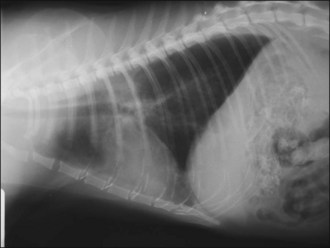

Pneumothorax

Closed pneumothorax usually results from leakage of air secondary to a lesion within the lung parenchyma, although it may also occur for example due to damage to the airways or oesophagus (Figure 28.2). Open pneumothorax involves loss of integrity of the thoracic wall (e.g. following penetrating trauma) while a tension pneumothorax occurs if a one-way valve is formed at the site of air leakage such that air taken in during inspiration leaks into the pleural space but cannot be expelled (Figure 28.3). The result is a rapid and potentially life-threatening increase in intrapleural pressure with severe respiratory and cardiovascular compromise and immediate thoracocentesis is required. In the author’s experience tension pneumothorax is rare.

image image

Figure 28.2 (a) Right lateral and (b) dorsoventral thoracic radiographs of a cat showing pneumothorax and pulmonary contusions following trauma.

image

Figure 28.3 Right lateral thoracic radiograph of a dog showing traumatic tension pneumothorax. The dog underwent cardiopulmonary arrest just prior to arrival at the hospital and the owner did not want resuscitation to be attempted.

Pulmonary contusions represent areas of alveolar and interstitial haemorrhage and oedema, and probably represent the most common thoracic injury in dogs and cats following trauma. Not all affected animals develop associated clinical signs and pulmonary contusions may occur with or without other thoracic injuries. Clinical signs may develop acutely or over several hours, and radiographic changes may lag behind clinical signs by up to 24 hours. Radiographic abnormalities (patchy or diffuse alveolar or interstitial lung changes) may persist for a variable period of time despite clinical improvement (Figure 28.4). There is no specific treatment for pulmonary contusions and management typically involves oxygen supplementation, cage rest, analgesia as indicated for concurrent injuries, minimal stress and time.

Figure 28.4 Right lateral thoracic radiograph of a cat showing pulmonary contusions.